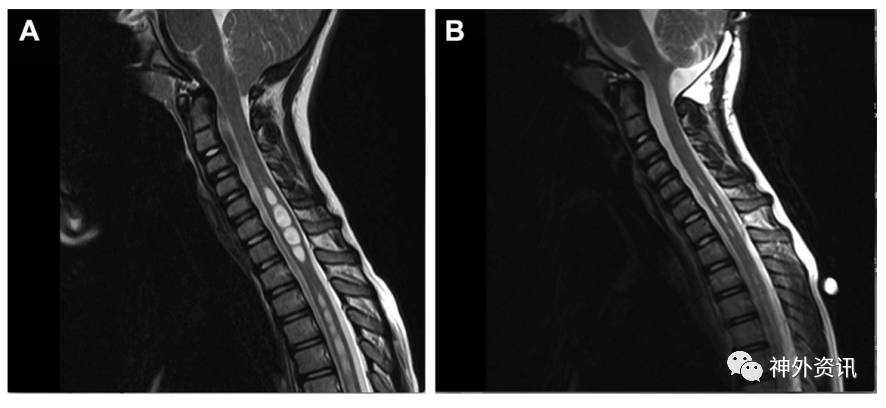

图1. 8岁CM1患者的颅颈交界和颈部MRI成像。A为术前;B为术后,颈胸段脊髓空洞症几近完全缓解。